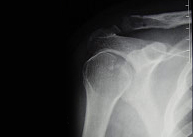

- Fracturas de la cabeza humeral

Las fracturas de la cabeza humeral o extremo superior del húmero afectan con mayor frecuencia al paciente de edad avanzada por su menor densidad ósea y en mayor proporción al sexo femenino. En el paciente joven se asocia con traumatismos de alta energía como accidentes de tráfico y deportes de alto riesgo en los que se pueda producir un impacto directo de gran violencia como escalada, motociclismo, ciclismo, esquí, rugby o fútbol americano.El tratamiento dependerá del tipo de fractura y grado de desplazamiento. Las fracturas desplazadas suelen requerir tratamiento quirúrgico. En este caso una cirugía destinada a una movilización precoz con un riesgo mínimo de complicaciones exige un gran conocimiento de la biomecánica articular así como un meticuloso manejo de los tejidos adyacentes al hueso.